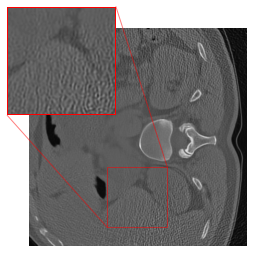

The methodology from DRUNet and its predecessor FFDNet [69] involves segmenting the input image into four distinct corner parts, each processed separately through the network. Zhang et al. [17] utilize images with identically distributed Gaussian noise, allowing for individual denoising of sub-images and recombination without noticeable artifacts at the patch boundaries. However, our application of this strategy in CT results in artifacts at the patch boundaries (cf. Figure 2(c)), showcasing a sudden shift from intense to subtle smoothing with the cropping strategy. This issue may arise because the errors in CT images are not simply Gaussian noise, but rather a more complex mixture of noise types, including Poisson noise that has been log-transformed and then backpropagated via FBP. For mitigating the artifacts, we modify the cropping approach of [69] by implementing padding in the output of the FBP to align with the network architecture. The DRUNet architecture operates solely on images sized as multiples of 24=16superscript24162^{4}=162 start_POSTSUPERSCRIPT 4 end_POSTSUPERSCRIPT = 16 due to its four downsampling steps, whereas the LoDoPaB-CT dataset comprises images of size 362×362362362362\times 362362 × 362, which does not conform to this requirement. To address this, we apply mirror padding to enlarge the images to 368×368368368368\times 368368 × 368 before passing them through the network and subsequently cropping them back to the original size of 362×362.362362362\times 362.362 × 362 . Figure 2 illustrates the suitability of the proposed strategy. (We point out that the image depicted in Figure 2 represents one of the most challenging reconstructions within the dataset.) For the 2016LDCTGC dataset, the images are sized at 512×512512512512\times 512512 × 512, which means they do not need additional padding and can be processed directly by the network.

Figure 2: An example highlighting the distinction between the DRUNet and FFDNet methodology of cropping versus the adapted padding strategy. (a) shows the low-dose FBP, while (b) displays the corresponding ground truth. (c) highlights the artifacts at the patch boundaries resulting from denoising on sub-images, whereas (d) exhibits artifact mitigation achieved through ommiting the partitioning into blocks.